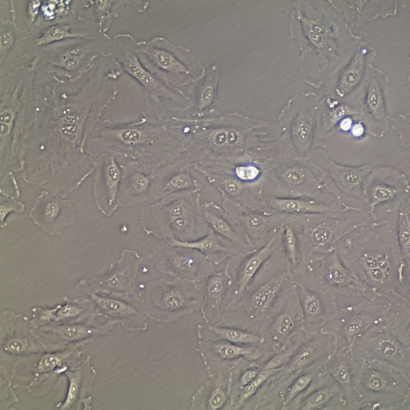

- Proliferation and Morphology: Normal cell appearance for 15 population doublings